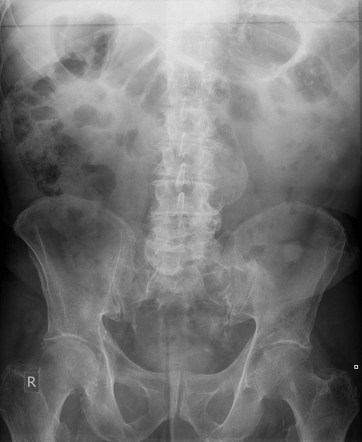

На обзорной рентгенограмме может визуализироваться дугообразная или веретенообразная тень с чёткими кальцифицированными краями, соответствующая расширенному участку брюшной аорты.

При значительном увеличении аневризмы выявляется смещение петель кишечника и других органов брюшной полости, что отражает компрессию соседних структур.

Контуры расширенного участка могут быть прослежены в виде изогнутой плотной тени, особенно если стенка аорты частично кальцифицирована.

В случаях крупных аневризм возможна деформация позвоночных тел за счёт давления со стороны пульсирующего образования.

Положение почек и мочеточников может быть изменено при выраженном расширении аорты и парааортальных структур.